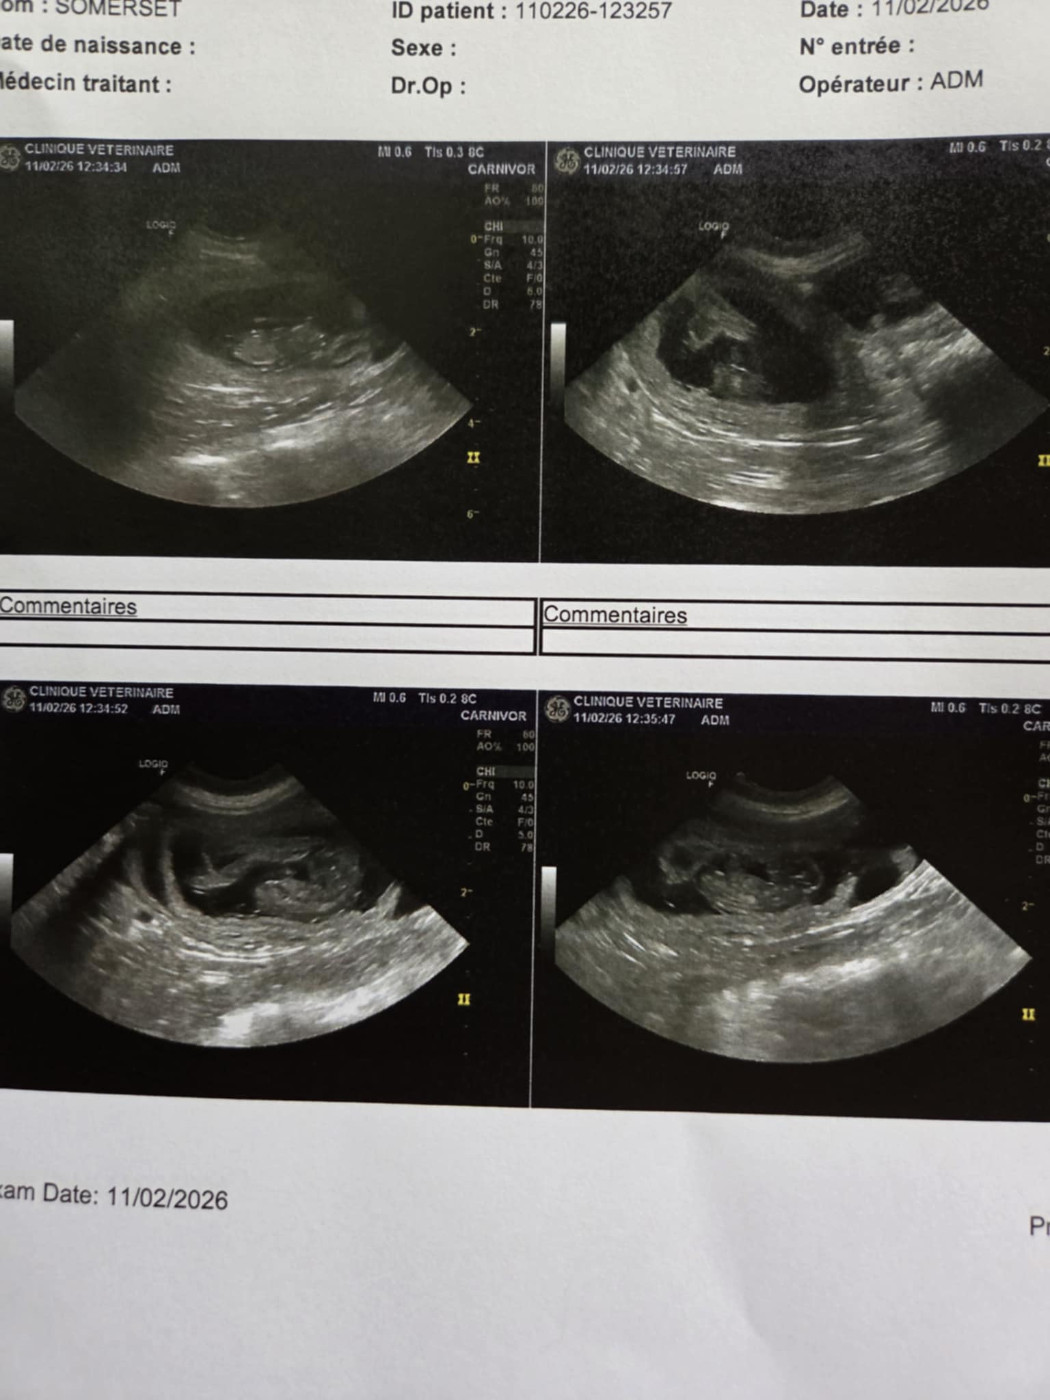

Pas de bébé avant la fin de l'année

13/05/2025

Je suis désolée pour les personnes qui attendaient depuis un moment un chiot de mon élevage mais après échographie cet après midi mes 2 femelles News et Opali...